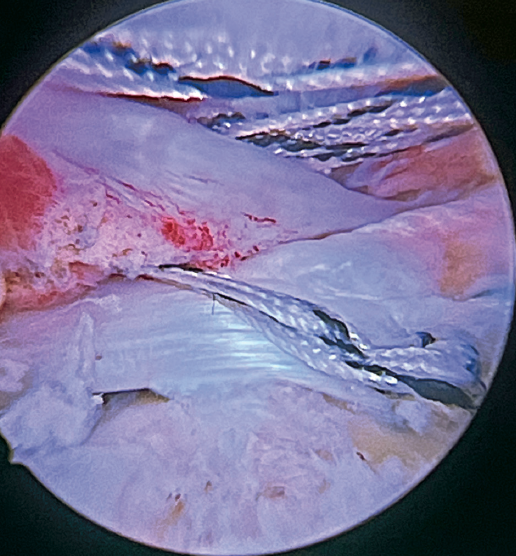

The greater tuberosity is then prepared with the bone drill, creating a bleeding bone surface to enhance tendon-bone healing, as this is where both cuff repair and augmentation with biceps will be carried out (Figure 1).

Previously, at intra-articular level, we assessed the quality of the LPB and its insertion in the supraglenoid tuberosity; from subacromial, having prepared the bony footprint on the greater tuberosity, we proceed to release the proximal portion of the tendon from the bicipital groove. The upper part of the transverse humeral ligament is sectioned to mobilize the LPB without damaging it (Figure 2). At this time, the mobility and integrity of the LPB is checked with tendon pulling forceps (Figure 3).